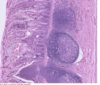

Parietal (A) & Chief Cells (B) in Stomach

Fundic gland - lumina (L) of the fundic glands can be recognized. The chief cells (CC) are granular in appearance and are much smaller than the round, plate like parietal cells (PC). Parietal cells, so their name imply, are located at the periphery of the gland. Slender connective tissue elements (CT), housing blood vessels, occupy the narrow space between the closely packed glands.